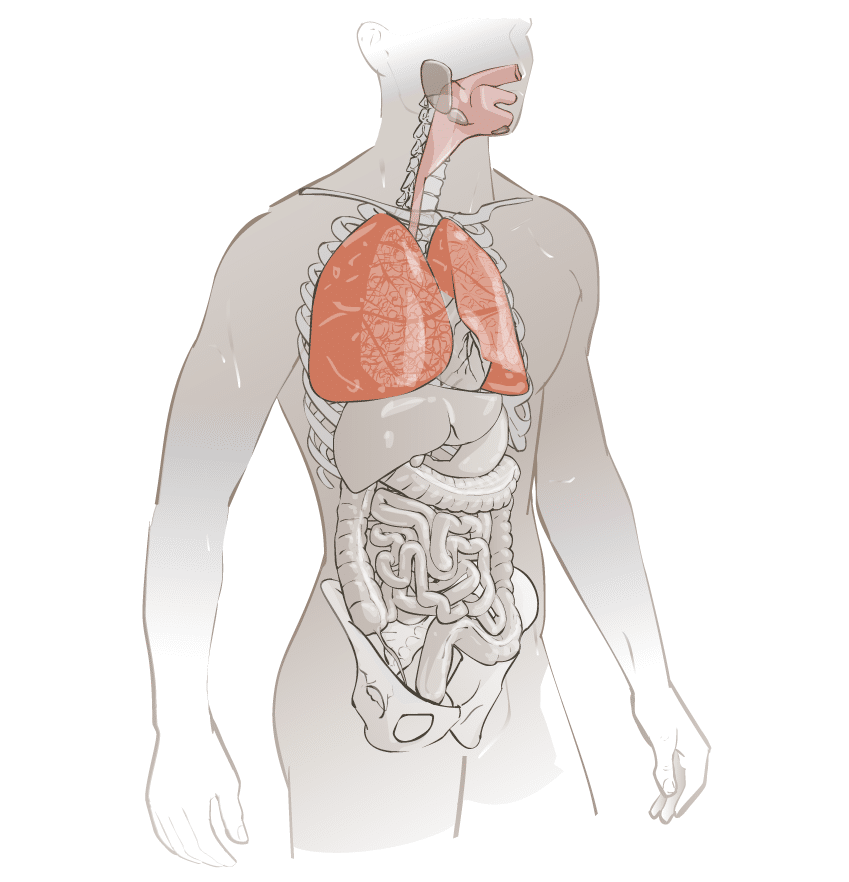

Voie respiratoire/aérienne